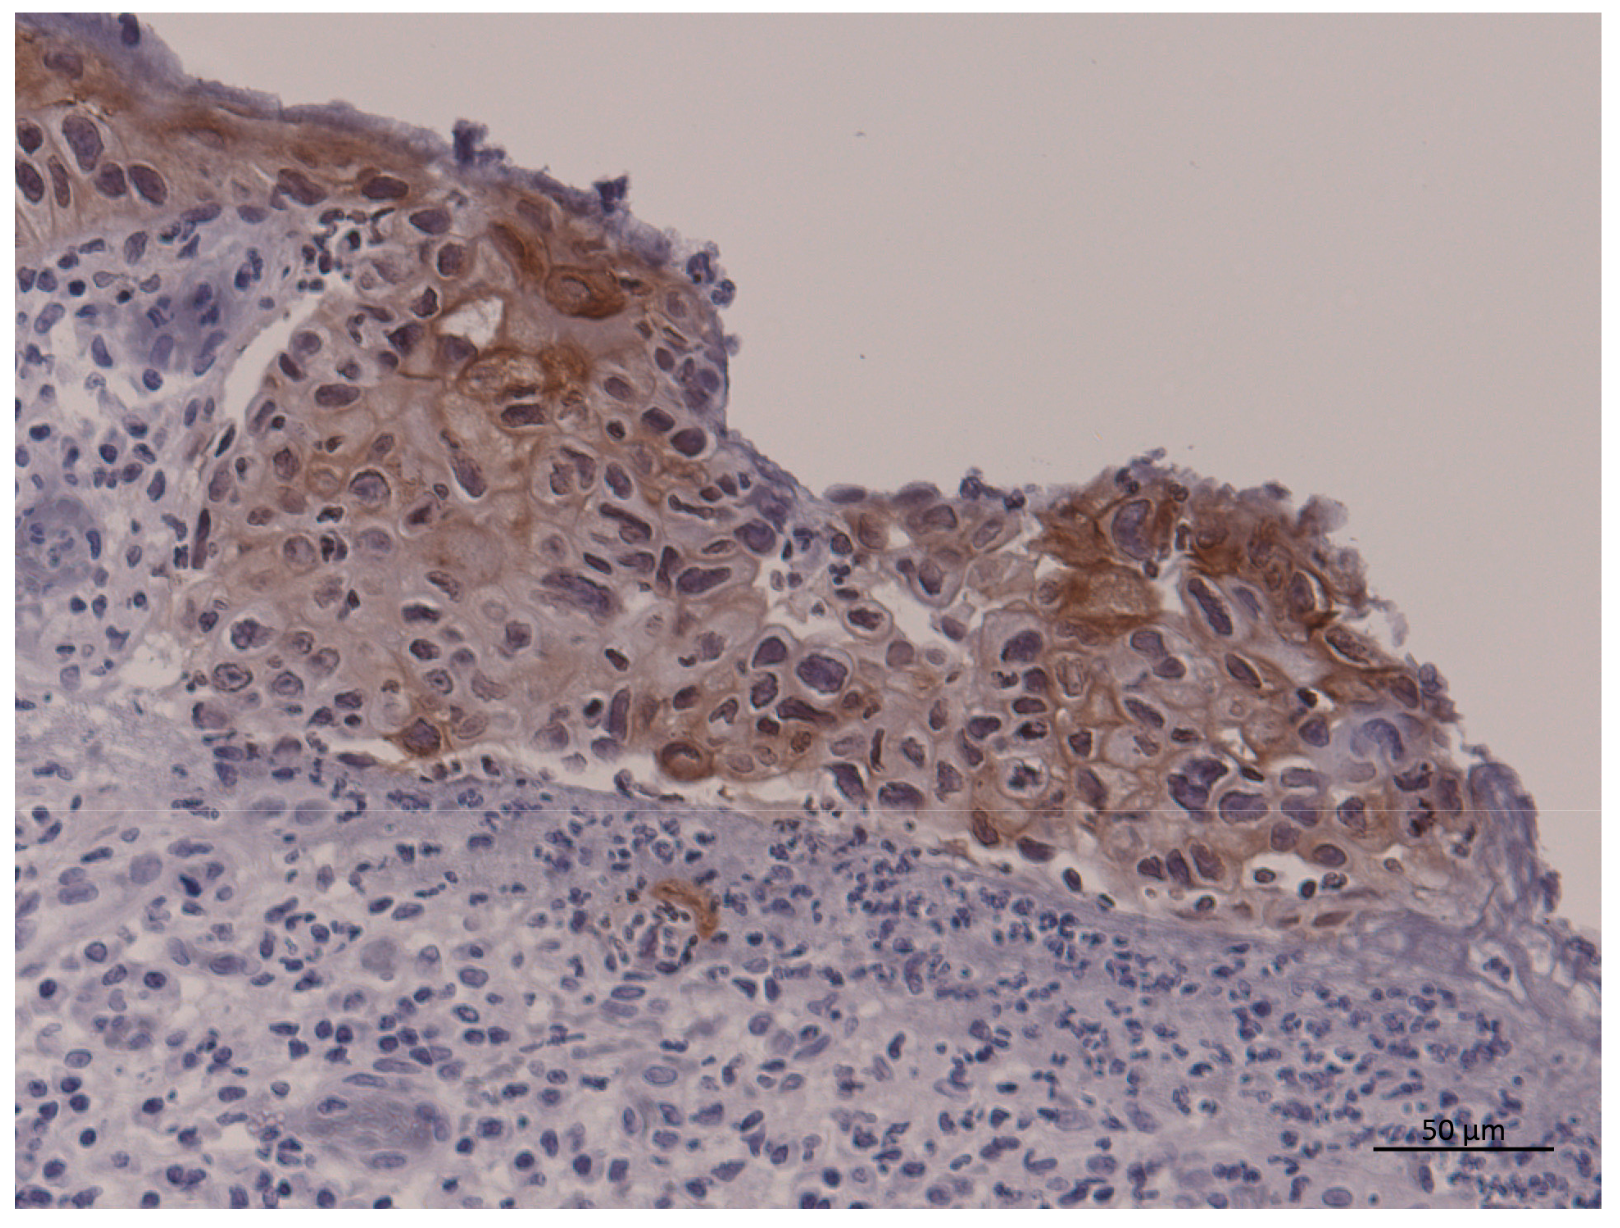

2.2. Immunohistochemical Analysis of PD-L1 Expression and PD-L1 SNPs (rs4143815 and rs2282055)

3.4. Expression of PD-L1